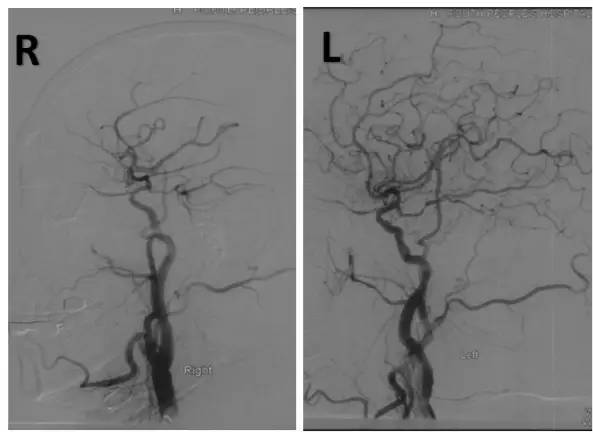

经微导管送入Transend(0.014” ,300cm)微导丝至基底动脉中段。撤出微导管沿微导丝送入Sprinter Legend RX球囊(2.0mm×15mm)准确定位于病变处预扩张,扩张后造影显示,前向血流改善,残余狭窄50%(图10)。

图10

撤出球囊导管,沿Transend微导丝送入XT-27微导管,撤出微导丝后沿微导管送入Neuroform EZ(3.0 mm×30mm)自膨式支架至病变处释放,造影显示前向血流好,TICI分级 3级,残余狭窄率约10%,同侧PICA显影良好(图11)。视察10分钟无变化后结束治疗。

图11